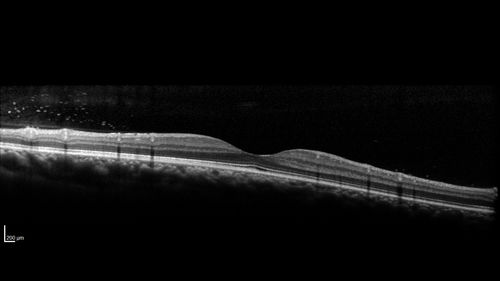

Eales Disease and fresh vitreous hemorrhage - 20 year old man

20 year old mane with fresh vitreous hemorrhage in the right eye.  At age 15 he had a PPV and laser in the left eye and laser in the right eye.  The vision is OD 20/80 PH 20/25, OS 20/25.  The left eye has a mild cataract.  He had prior testing for coagulopathies which was negative.  Testing done for syphillis and TB was negative.  Additional laser was done to prevent further bleeding in the right eye.